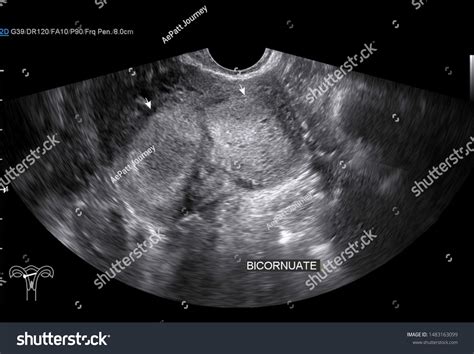

Diagnosing a Bicornuate Uterus

Diagnosing a bicornuate uterus typically involves a combination of imaging techniques. The most common methods include:

• Ultrasound: A transvaginal ultrasound can provide detailed images of the uterus and help identify any structural abnormalities.